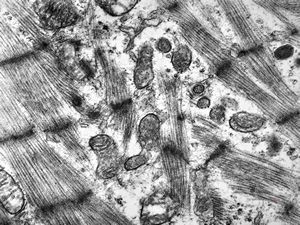

M,47y. | hypertrophic cardiomyopathy - left ventricle